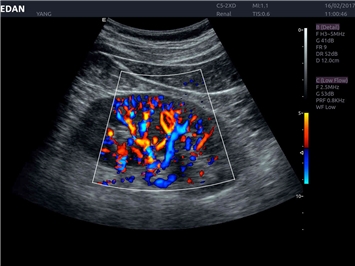

EDAN Acclarix LX4

Расширьте свои представления. Использование усовершенствованной платформой Acclarix система LX4 обеспечивает непревзойденную четкость изображений и интеллектуальный рабочий процесс для всех пользователей, являясь при этом наиболее экономичным решением.

EDAN Acclarix LX4 представляет собой инновационную ультразвуковую систему, построенную на усовершенствованной платформе Acclarix. Сочетание высокого качества визуализации с интеллектуальным рабочим процессом делает эту систему оптимальным выбором для клиник, ценящих эффективность и экономичность.

Области применения:

Система Acclarix LX4 оптимально подходит для:

• Общей визуализации

• Кардиологических исследований

Трехмерная реконструкция ЦДК:

Да

Color 3D: